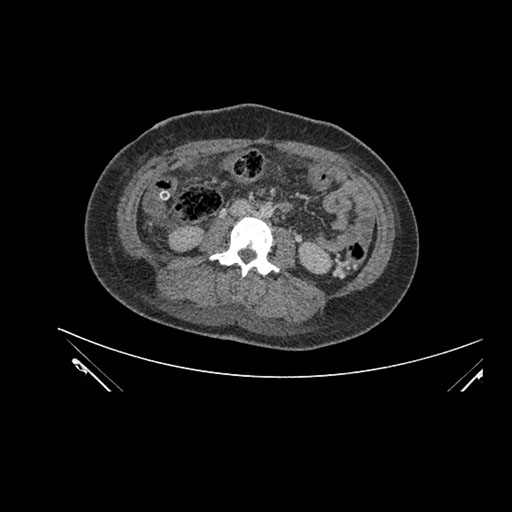

Imaging Analysis

Look through the patient's CT scan to identify any areas of concern for the necessary procedure.

Axial Arterial

Axial Venous

Based on initial findings, which issue(s) would you be most concerned about?